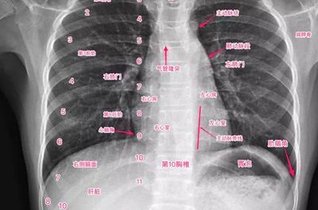

正常胸片影像图片

概述胸片即胸部X线片,正常胸部X线片影像主要用于疾病的筛查、定位和治疗后复查等。正常胸部X线片影像可看到胸部脏器和胸壁等部位的正常结构表现。结构正常胸部X线片影像可看到胸廓、...